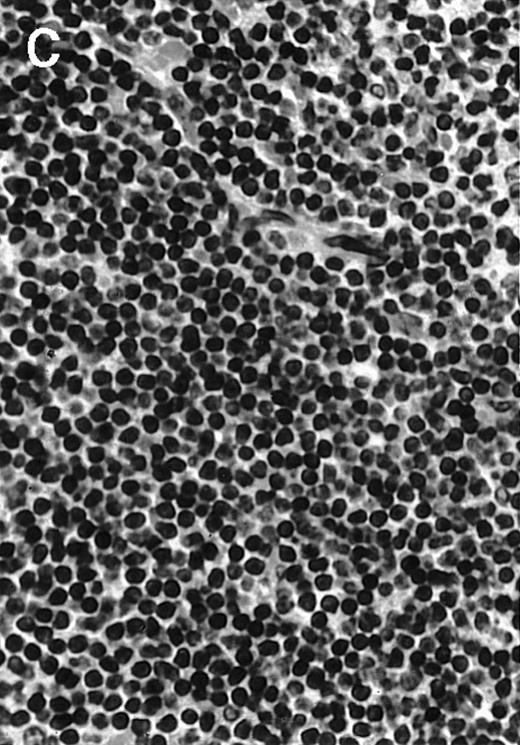

To analyze expression of the human CD40L protein in murine tissues, samples from the small intestine, colon, liver, and spleen were analyzed by HE staining as well as immunohistochemistry. We found that in mice immunized with ST40L, the Peyer's patches were prominent (Figure 1A), and the majority of cells in the Peyer's patches could be seen to express the human CD40L protein (positive: brown or yellow color; negative: blue color) (Figure 1B). There were a few CD40L+ cells in spleen, but not in liver. In contrast, human CD40L was not detectable in the Peyer's patches of mice treated with ST (Figure 1C). To further confirm the secretion of human soluble CD40L by transfected murine cells into the sera, we next examined it by ELISA (Figure 2). Human soluble CD40L protein was detectable only in BALB/c mice treated with ST40L with or without administration of BCL cells, but not detectable in mice treated with ST and/or BCL cells. The level of soluble CD40L protein in the sera peaked at 1 week after oral administration and was detectable until 7 to 8 weeks.

Presence of transduced human CD40L protein in mice treated with ST40L.

(A) HE staining of intestine ( × 100) of BALB/c mice killed 1 week after oral administration of ST40L. (B) Immunostaining of Peyer's patches using antihuman CD40L Ab (×400) of BALB/c mice killed 1 week after oral administration of ST40L. (C) Immunostaining of Peyer's patches using antihuman CD40L Ab (×400) of BALB/c mice killed 1 week after oral administration of ST.